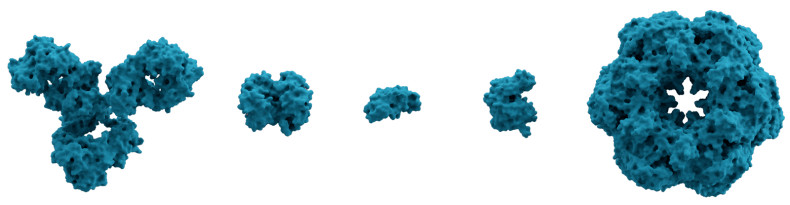

Notably, proteins are a perfect example of the synergy between form and function. The physical 3D structure of a protein determines its function. Therefore, to function correctly, a protein must take the correct 3D shape. Proteins comprise strings of amino acids. Consequently, a highly specific sequence of amino acids creates the correct protein shape. Proteins take many different shapes, as you can see below.